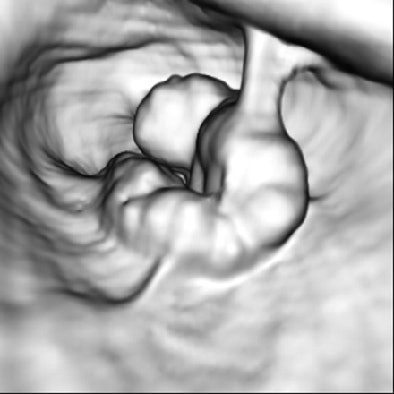

| Above, colonoscopic view and surface and vascular virtual endoluminal images for representative case of advanced colorectal cancer in a 60-year-old woman. Colonoscopic view shows advanced cancer in sigmoid colon. Below, surface virtual endoluminal view in the same patient shows lesion. Bottom, vascular virtual endoluminal image clearly shows blood pooling of tumor and vessels. Iinuma G, Moriyama N, Satake M, Miyakawa K, Tateishi U, Uchiyama N, Akasu T, Fujii T, Kobayashi T, "Vascular Virtual Endoluminal Visualization of Invasive Colorectal Cancer on MDCT Colonography" (AJR 2005; 184:1194-1198). |